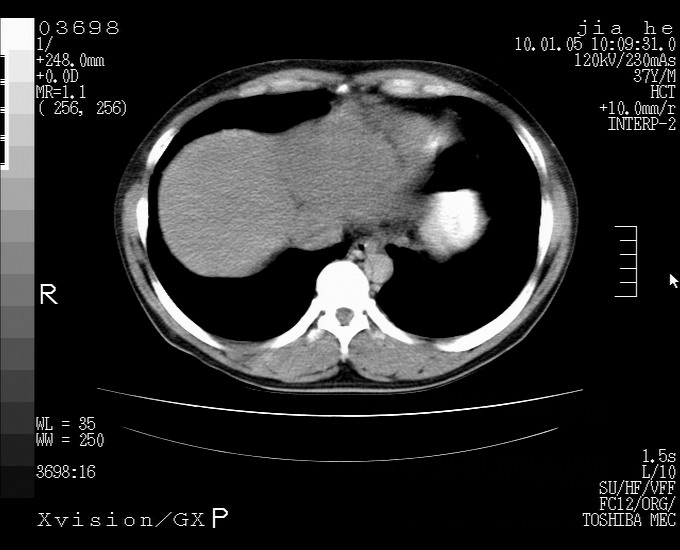

标题: CT23988:男,40岁,B超提示腹部肿物,请各位老师给看看。 [打印本页]

标题: CT23988:男,40岁,B超提示腹部肿物,请各位老师给看看。

左叶够大的,且与胰腺欠清晰,请增强扫描

肝左叶增大,建议增强扫描。

肝癌并腹膜后淋巴西结转移

1.该患者有腹部手术史

2.脾大,肠系膜密度增高,有多发索条影,胰腺边缘毛糙,腹膜增厚,推测有肝硬化,门脉高压,腹膜炎和/或胰腺炎

3.肝左叶巨大站位,并腹腔淋巴结肿大,肝癌或肝间叶来源恶性肿瘤,也不排除大网膜间质瘤侵及肝左叶

建议:增强或磁共振

肝癌并腹膜后淋巴结转移

外生性肝癌并腹膜后淋巴西结转移!

还有个异位胆囊。临床资料太少,肿瘤、左叶发育异常、肝硬化。不过看密度是个低密度为主的,新生物倾向于第一位。强化吧!

考虑肝左叶外侧段癌并腹膜后淋巴结转移.建议增强进一步检查.